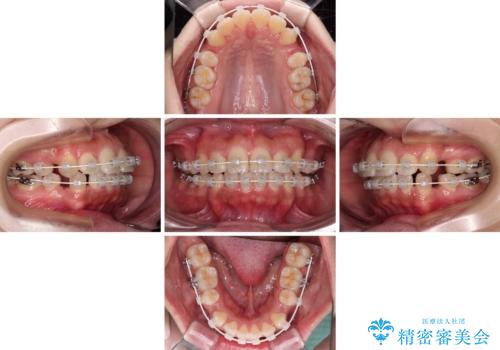

- 矯正装置

- 審美装置

- 前歯の出っ歯と口元の閉じにくさを気にして来院された患者様です。

口元を積極的に引っ込めるために、上下左右の小臼歯4本を抜歯することとしました。

4本の歯を抜歯したことで、飛び出していた口元が引っ込み、横顔の印象が大きく改善されました。